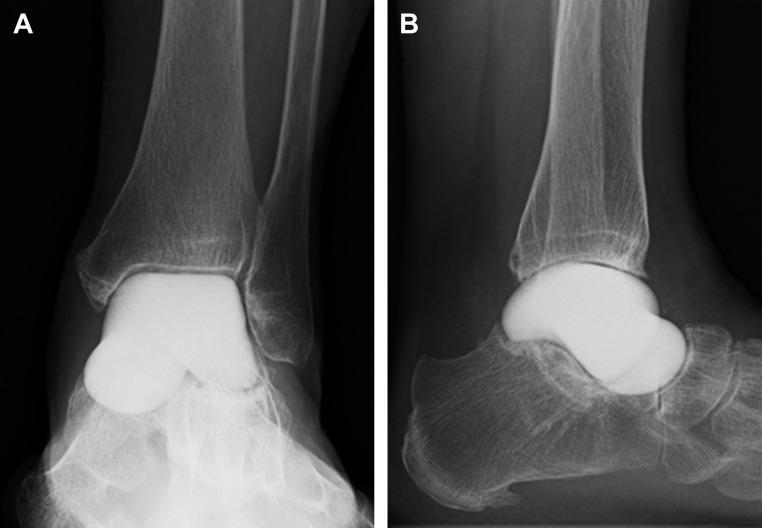

Avascular necrosis tends to occur in the talus because of poor blood supply caused by the extended coverage to the articular cartilage on its surface. Treatment is conservative in the earlier stage of this disease; however, surgical treatment is usually indicated in the advanced stage. Nonunion, leg length discrepancy, or hindfoot instability may occur in patients treated with ankle or tibio-talo-calcaneal fusion. Arthroplasty using a customized total talar prosthesis designed using the computed tomography image of contralateral talus has the potential advantages of weightbearing in the earlier postoperative phase, prevention of lower extremity discrepancy, and maintenance of joint function.